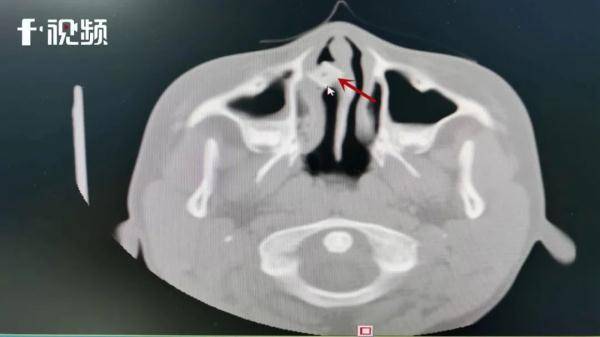

▲小邓鼻腔内发现明显异物

完善相关检查后 , 医生在小邓鼻腔内发现明显异物 , 且异物周围已长满肉芽引发了感染 。

“给患者做了个前鼻镜检查 , 明显看到鼻腔有肿块 , 且肿块边缘被肉芽包裹 , 经过进一步检查发现 , 异物卡在患者下颌窦窦口位置 , 异物形状类似方形色子 , 手术取出发现是一个打麻将用的色子 。 ”刘刚表示 。